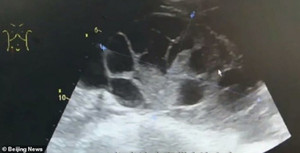

Cách đây không lâu, Tòa án Nhân dân quận Bạch Vân, thành phố Quảng Châu, tỉnh Quảng Đông (Trung Quốc) đã xét xử vụ án nữ sinh họ Lại tham gia môi giới bán trứng bán thời gian. Công việc của Lại là đưa những người muốn bán trứng đến nơi phỏng vấn, khám sức khỏe, siêu âm. Cuối cùng, Lại bị kết án 10 tháng tù giam.

Bác sĩ Chu Y Mẫn, Giám đốc khoa Nội tiết Sinh sản tại Bệnh viện Phụ sản, thuộc trường Đại học Y khoa Chiết Giang (Trung Quốc) chia sẻ, chọc hút buồng trứng sẽ gây ra tình trạng đau bụng, nôn mửa, cổ trướng nặng, máu đông, suy thận, phù phổi, tắc mạch máu não, thậm chí là tử vong.

Bác sĩ Chu Y Mẫn cũng nhấn mạnh: "Trong quá trình chọc hút trứng sẽ dẫn đến hoại tử máu, thiếu máu cục bộ ở buồng trứng. Nếu không phát hiện kịp thời thì buồng trứng và ống dẫn trứng sẽ bị hoại tử, có thể phải cắt bỏ. Cắt bỏ một bên buồng trứng tương đương với mất một nửa khả năng sinh con, cắt bỏ toàn bộ buồng trứng đồng nghĩa với chuyện hoàn toàn mất khả năng sinh sản".